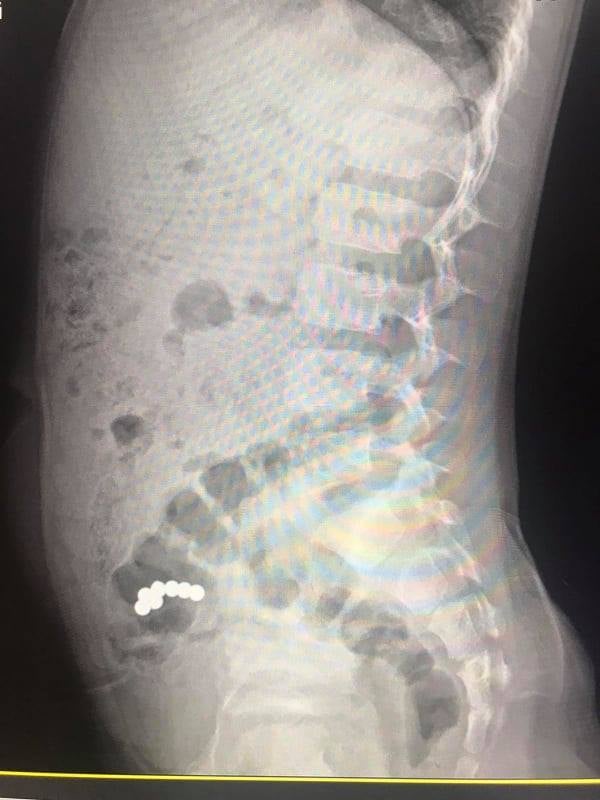

Нещодавно в хірургічне відділення обласної лікарні поступив хлопчик віком 5 років через 17 днів після ковтання дрібних магнітних кульок. При госпіталізації скарги були відсутні. Під час рентгенологічного дослідження діагностовано наявність магнітів в кишечнику, які не просуваються впродовж 10-ти днів. Відсутність пасажу магнітів о кишечнику стало показанням до оперативного втручання.

Під час операції виявлено інтимне зрощення стінки тонкої кишки, де розташовані 4 магніти, зі стінкою сліпої кишки, де виявлено 3 магніти. Тож, медики провели клиновидну резекцію тонкої та сліпої кишки, видалення магнітів, ушивання стінки тонкої та сліпої кишки.